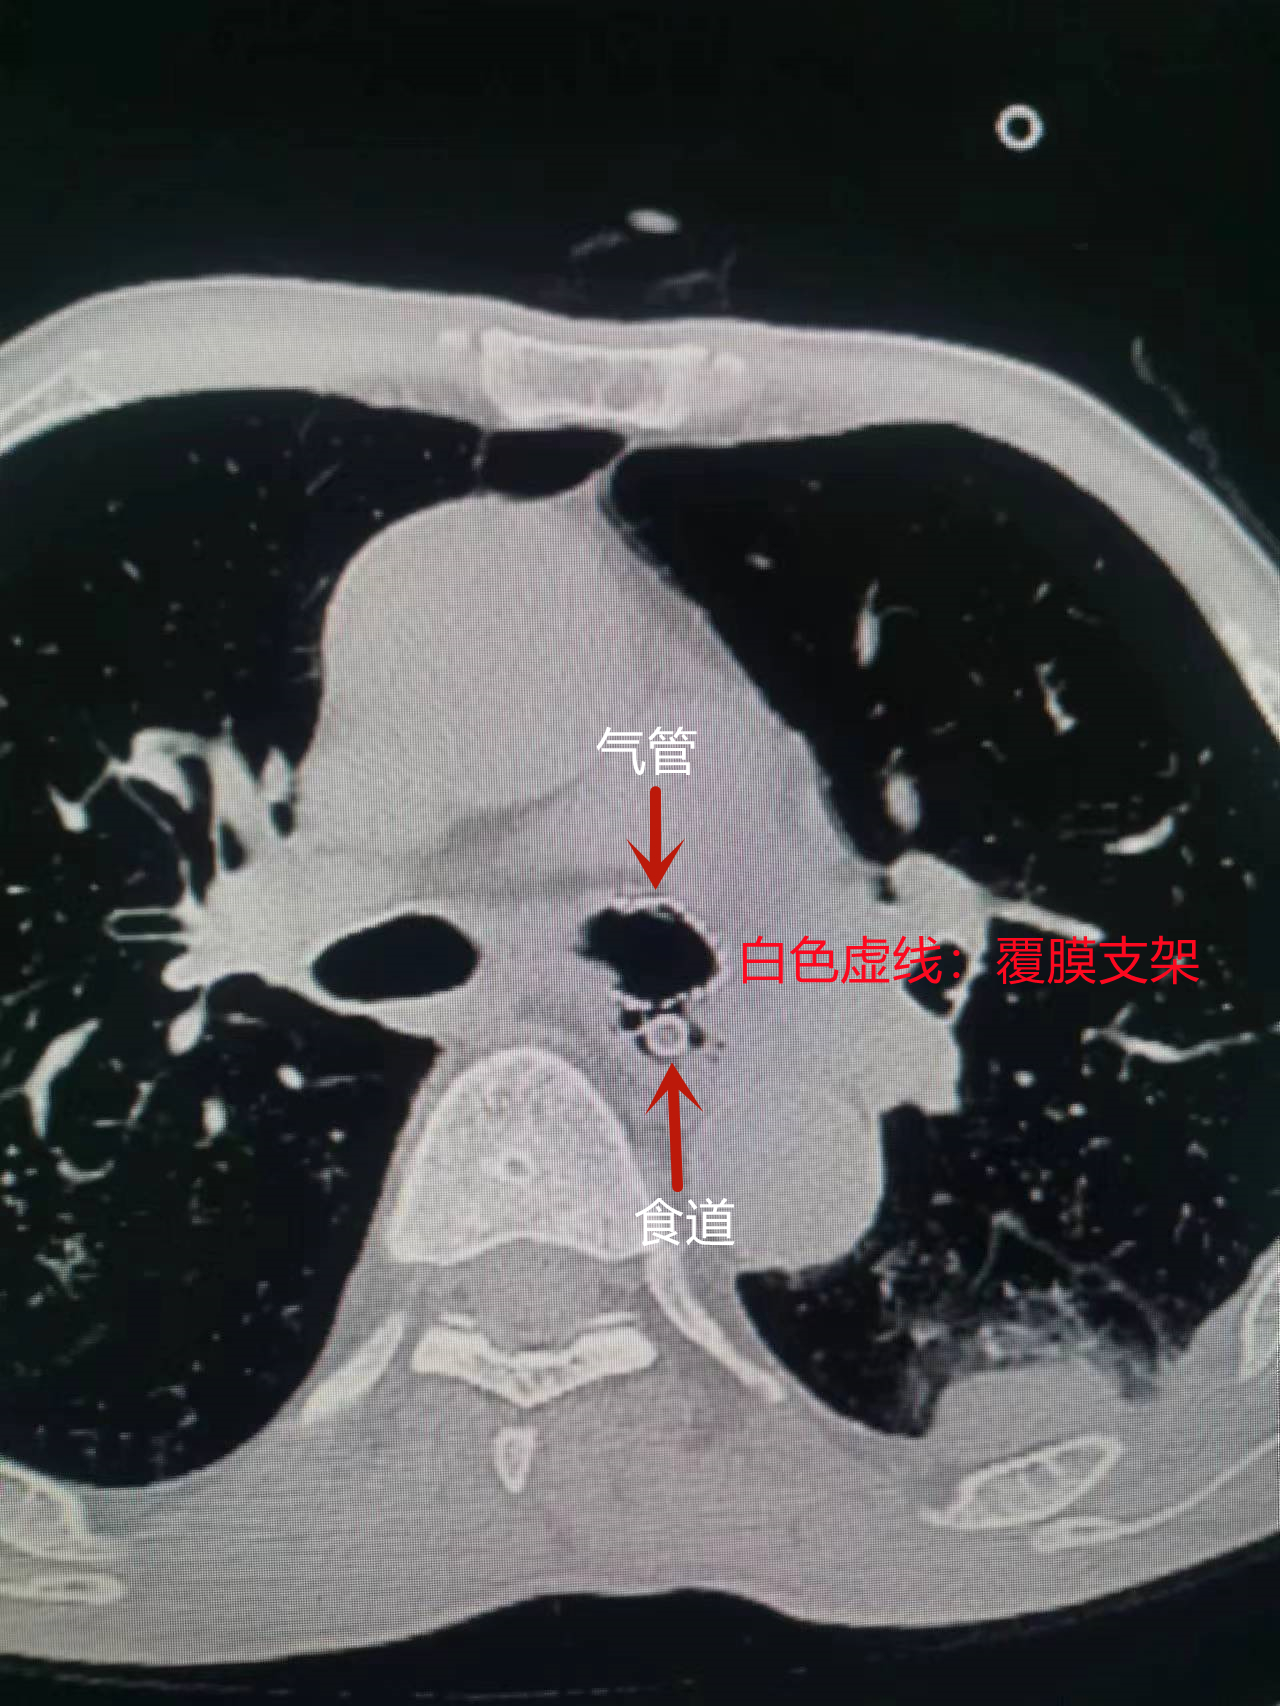

气管镜下置入气管覆膜支架

术后CT

经过胸部CT和纤支镜等检查,患者食管气管瘘的诊断得到了明确。“正常食管位于气管后方,彼此间有疏松组织间隔,保证进食、呼吸两条通道互不影响。然而,患者现在食管和气管之间形成了异常通道,导致进食后食物和消化液经过异常通道进入气管,就会出现剧烈咳嗽,非常难受,并引起吸入性肺炎,咳脓痰和呼吸困难,严重的可能危及生命。”青措主任详细、耐心地向患者家属解释道。

因张大爷的瘘口发生在距离隆突仅0.5cm的左主支气管,瘘口位置险要,安置难度大,纤支镜团队在取得家属和患者的同意,经过充分术前准备,并邀请华西医院程德云教授现场指导下,由张琼主任医师、青措副主任医师及王珂主治医师三位医生相互协作,在团队密切的配合下,手术一气呵成,支架植入位置精准,扩展良好,贴合完好,瘘口被完全封堵,支架植入时间仅用时3分钟。术中,患者各项生命体征平稳,术后,患者呛咳、咳痰等症状得到了明显改善,配合药物治疗,张大爷的肺部感染得到了明显的控制,避免了呼吸道梗阻的发生,为今后进行长期气道管理、防治感染以及后续的营养支持争取了机会。